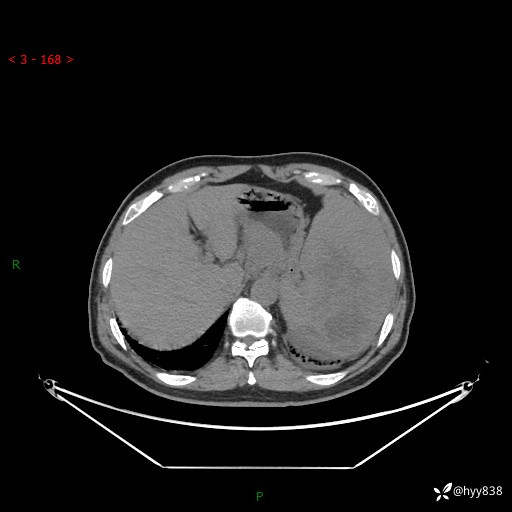

上腹部CT平扫

增强(动脉期+静脉期)